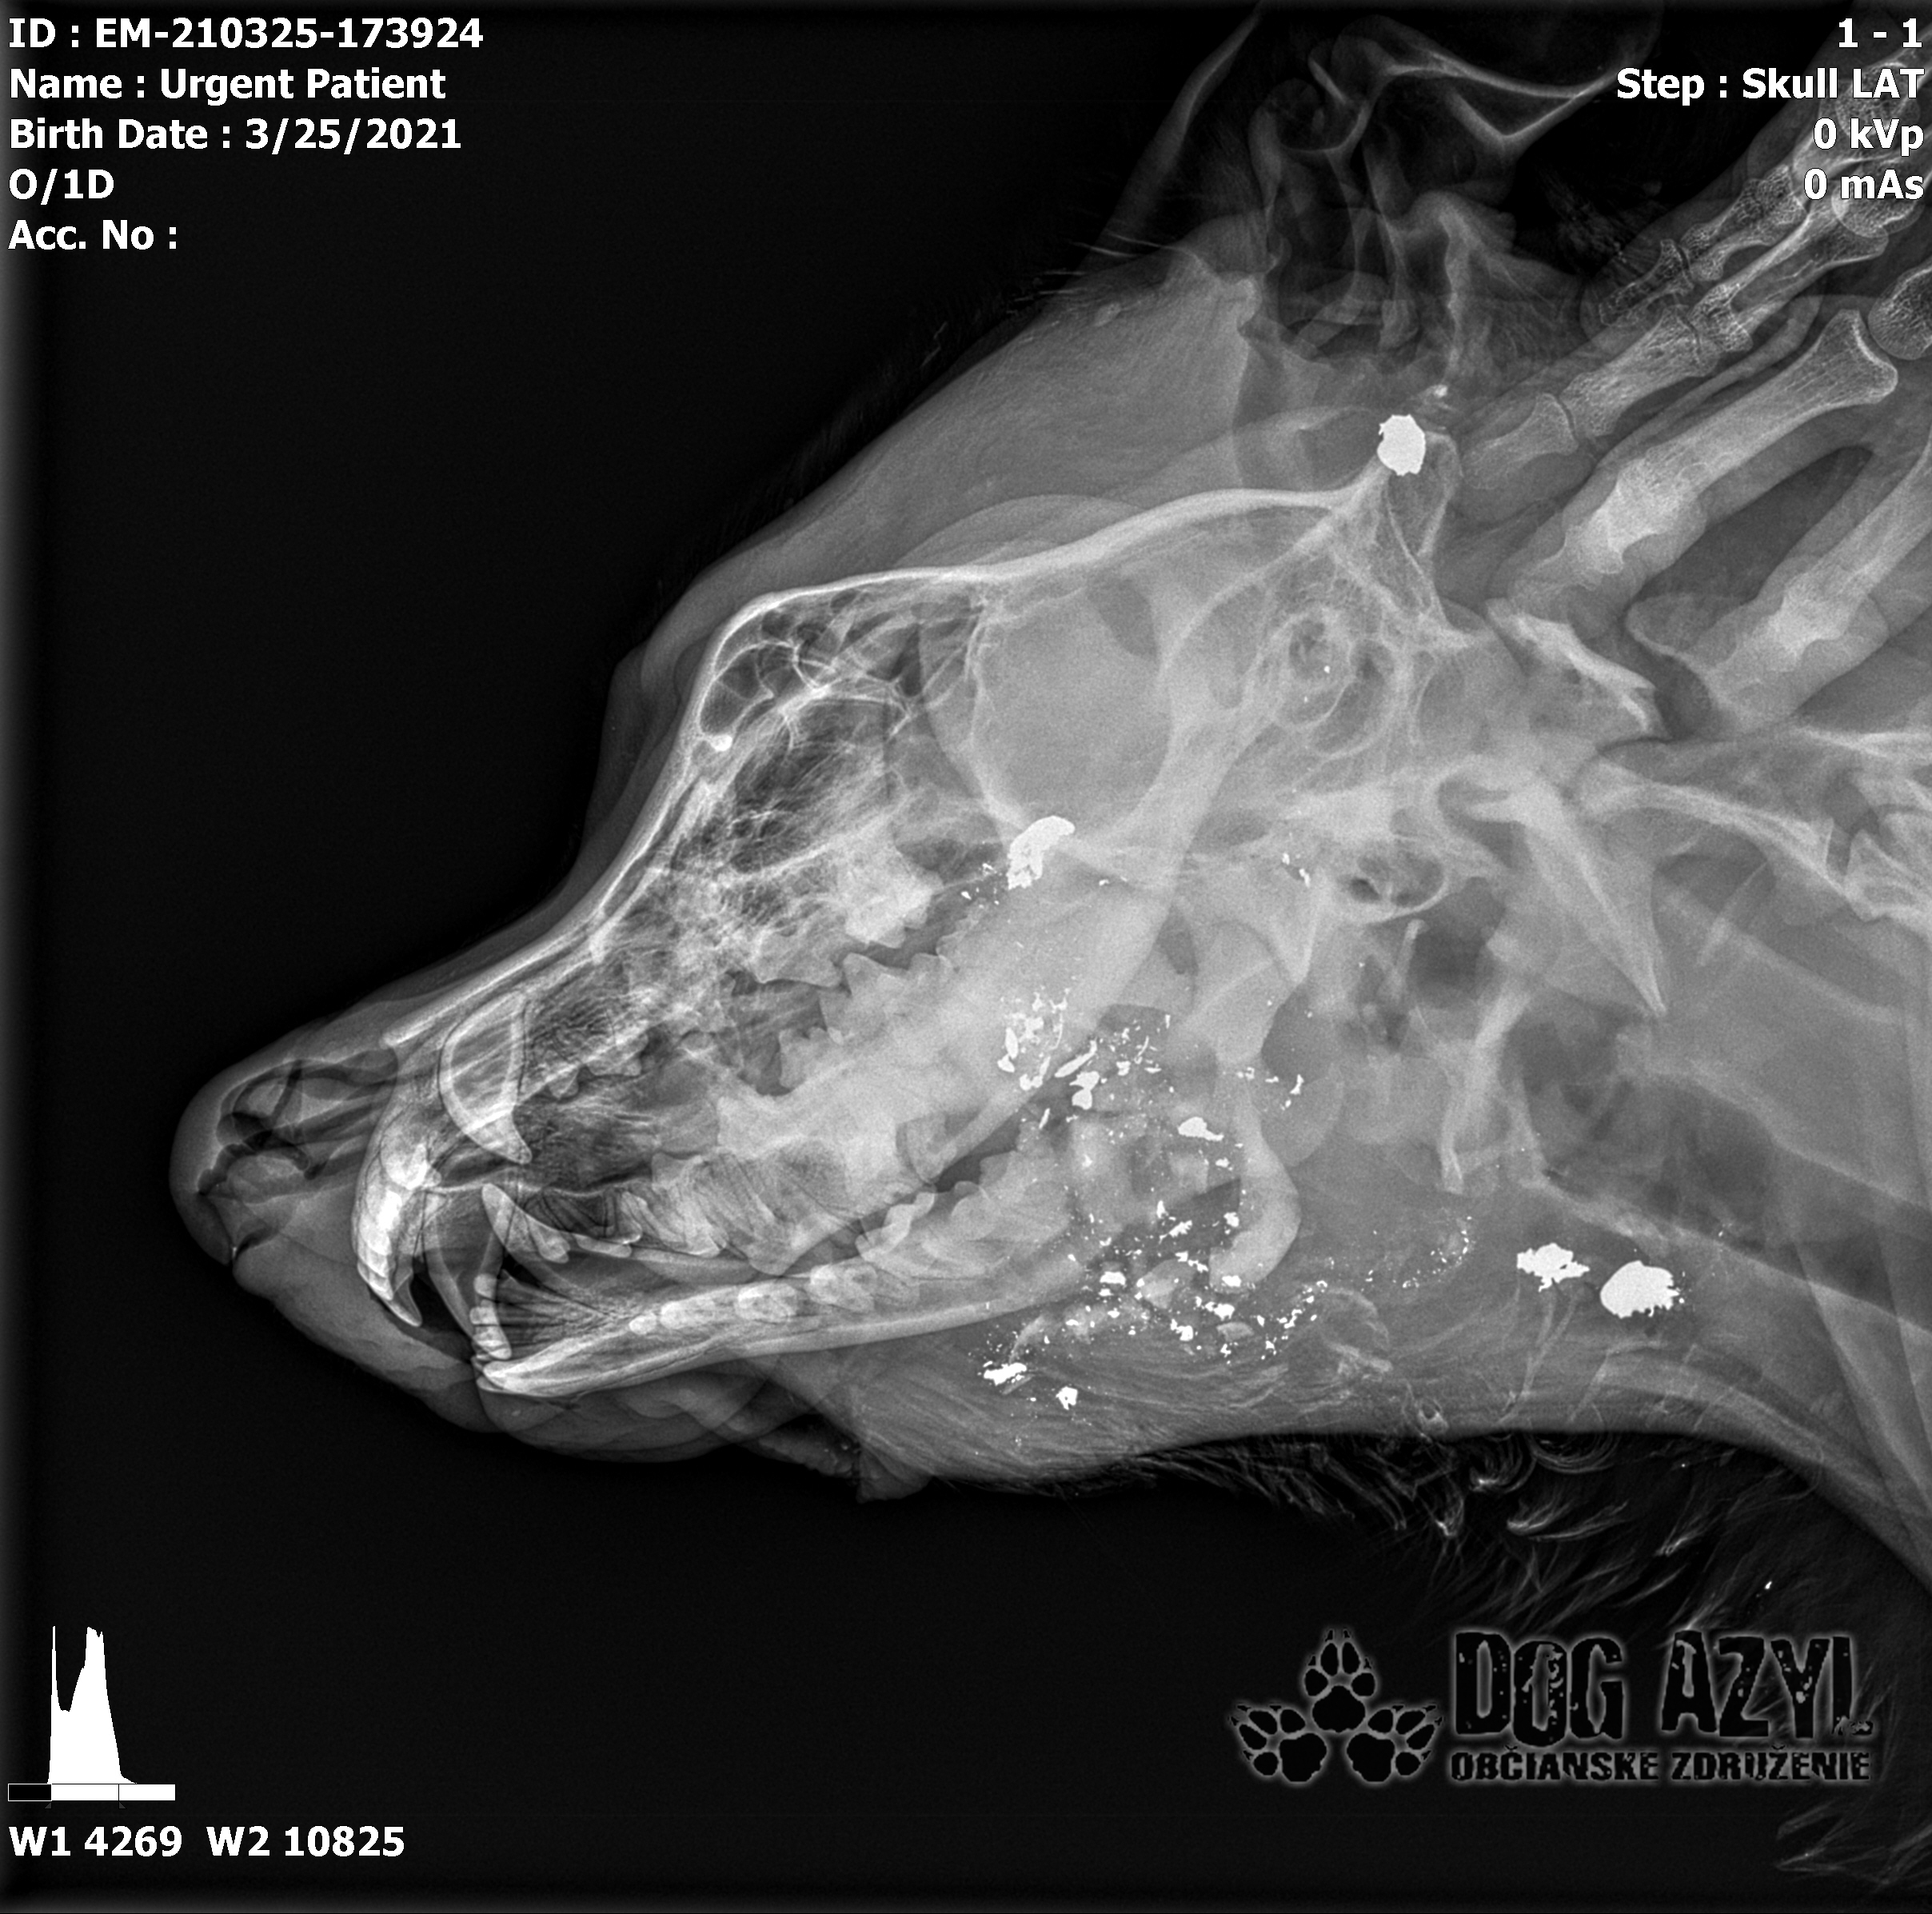

Ona ležala na ľavo, on na pravo od zavesenej šunky, ktorá mala zrejme slúžiť ako návnada, aby sa terče nehýbali.. Uprostred ničoho, bez svedkov, bez dôkazov... Pár kvapiek krvi na ceste.. Ona to schytala jedinou ranou do srdca.. On má roztrieštenú sánku, schytal to do hlavy..

/Strašne to chcem dopísať tak, aby to bolo čitateľné a pochopiteľné, ale celá sa klepem od zlosti a nevidím cez slzy.../ Lebo Ona už meno nikdy nebude mať.. On dostal meno Baris a bojuje o život!!! Má dolámanú sánku a je v šoku!!! Dostal prvú pomoc, analgetiká a priorita bola znížiť jeho teplotu z 41,4°C!!!

Ústami nevie pohnúť, jazyk si nevie ovládať a tak sa sám nedokáže schladiť ani napiť. Podľa RTG sú srdiečko a pľúca v poriadku, ale vôbec nemá vyhraté!!! Niekto chcel Barisa zlikvidovať, ale my za neho budeme bojovať do posledného dychu!!! Zajtra bude prevezený na veterinárnu kliniku Sibra centrum, kde ho čaká team špecialistov z oblasti chirurgie, neurológie a ortopédie. Ak je čo i len najmenšia nádej, že Baris bude môcť žiť, tak BARIS BUDE ŽIŤ!!!